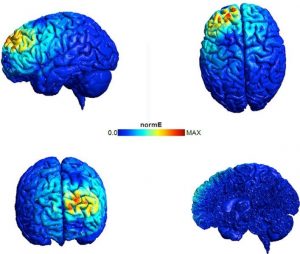

2- شکل بالا نمودار فعالیت الکتریکی ایجاد شده در مغز هنگام استفاده از TMS بر قشر پری فرونتال چپ می باشد. هر تصویر مغز را از زوایای مختلف نشان می دهد. رنگهای سرد حاکی از افزایش بار الکتریکی منفی و رنگ های گرم تر نشان دهنده ی افزایش بار الکتریکی مثبت می باشد. این تصاویر به وضوح نشان می دهد که چه مقدار از مغز توسط TMS اعمال شده روی پوست سر تحریک می شود.